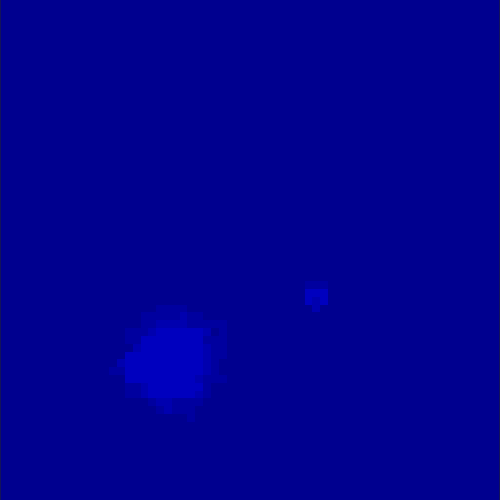

In two different tests we fixed the number of events counted by the detector equal to (resp. ) times the average concentration in one pixel. The resulting sinogram images of the accumulated counts in each bin are shown in figure 9.

Based on the sinogram data we applied the proposed algorithm in order to reconstruct the original image sequence. The results for both test cases are shown in figure 10.